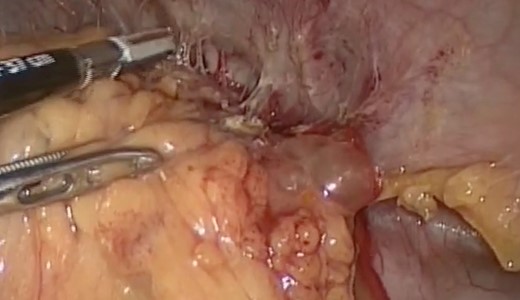

Intraoperative findings included extensive inflammation involving the inferior half of the spleen, the splenic flexure of the colon and the distal pancreas, as well as the abscess in question which contained approximately 10 cc of purulent material (Figs 3 and 4). The final surgical specimen included the entire spleen and the histologic report of pancreatic tissue compromised by the abscess. The patient was transferred to the surgical ICU for 24 hours. The following day, the blood cultures taken on admission grew an extended spectrum beta-lactamase producing Escherichia coli resistant to carbanemic agents and sensitive to tigecycline. The antibiotic regimen was modified accordingly, and after 7 days the patient was discharged symptom-free and with a plan to complete 15 days of tigecycline at home.

Splenic mass, inflammatory adherences from the major momentum to the spleen, colon and diaphragm.

Inflammatory tissue dissection and drainage of the splenic abscess.